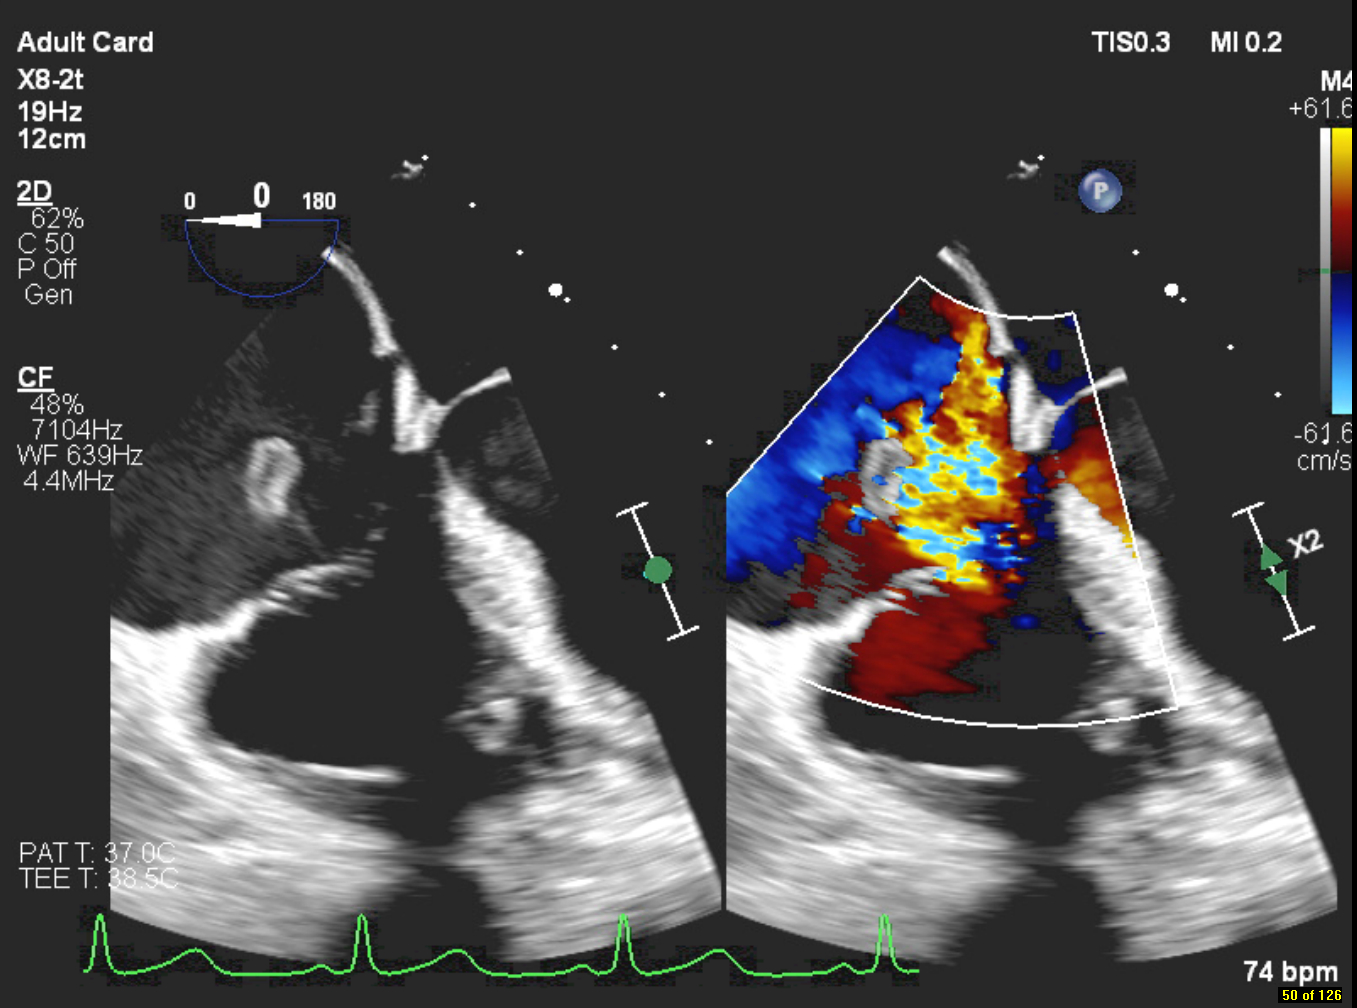

A 51-year-old female with ESRD on hemodialysis via a right tunneled catheter presented with fever and left knee pain. She was febrile and septic on admission; blood cultures grew MRSA. IV vancomycin was started, and the catheter was removed. Initial transthoracic echocardiography (TTE) showed no vegetations or intracardiac masses. CT chest post catheter removal revealed vegetations on the tricuspid valve, in the SVC, and right brachiocephalic vein with septic pulmonary emboli. Transesophageal echocardiography (TEE) showed a large, mobile, multilobular vegetation on the anterior tricuspid leaflet extending into the right atrium and SVC, with severe tricuspid regurgitation. She underwent transcatheter debulking with AngioVac, successfully removing vegetations from the tricuspid valve, SVC, brachiocephalic vein, and right heart. No residual vegetations were seen post-procedure. MRSA was also isolated from the left knee aspirate; she underwent incision and drainage. Blood cultures cleared following catheter removal and AngioVac intervention. She was discharged to a skilled nursing facility for rehabilitation and completed a six-week course of IV vancomycin.